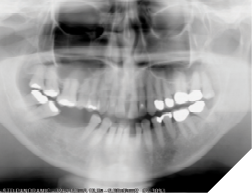

This type of tooth movement occurs during the period of remodeling of the periodontal structures soon after the active orthodontic appliances are removed. In the absence of compliance with the orthodontic retainers, the tooth movements are seen within weeks after the removal of the orthodontic appliances (Fig. 8).

Fig. 8A

Fig. 8B